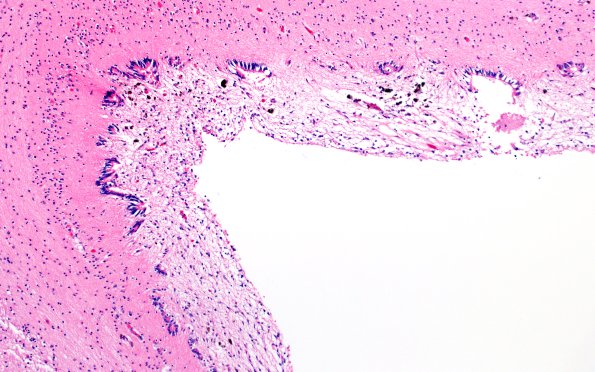

29B6,7 The adjacent ependymal lining shows significant granular ependymitis. (H&E)